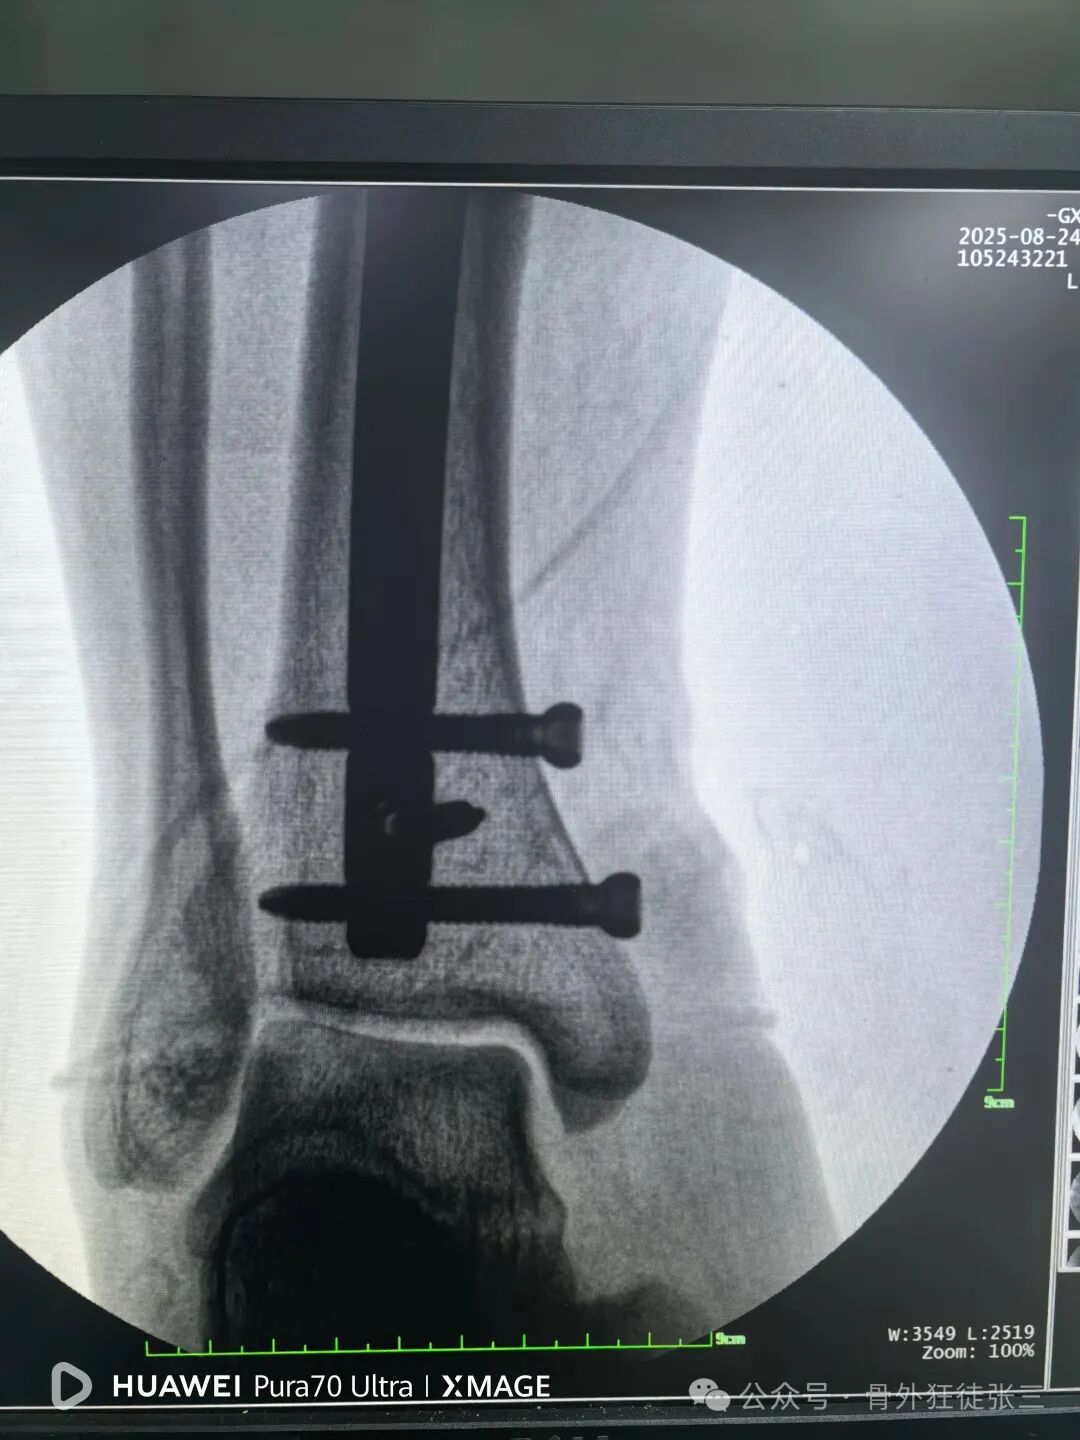

锁近端两枚锁钉

所以直接就没有打静态孔

尾帽顺利锁定